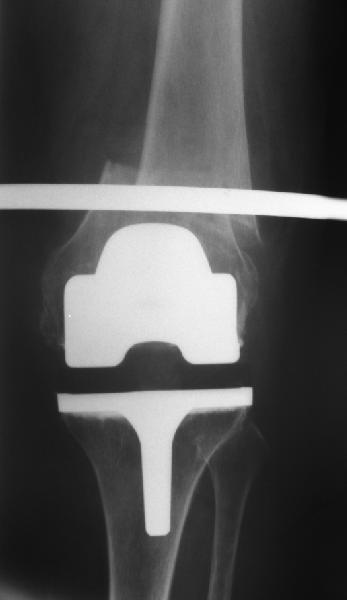

Поступила больная с перипротезным переломом

Перипротезный перелом у пациентки 67 лет . Эндопротезирование год назад . Сопутствующие нарушения ритма сердца и вес 120 кг при росте 185 .Думаю о мыщелковой пластинке с угловой стабильностью рыбинского исполнения остальное больной не потянуть . Заранее всем спасибо !

То, что планируется - наиболее распространенный подход. Еще менее инвазивный вариант - закрытый антеградный интрамедуллярный остесинтез. Мы используем гвозди, которые выпускаются предприятием ЦИТО, т.е. недорогие. Там в дистальное отверстие можно ввести 3 винта (2 снаружи и один навстречу), еще и угловая стабильность получается.